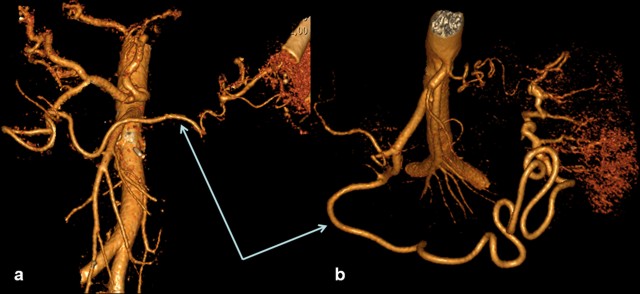

The spleen maintaining its arterial blood supply is the case when the gastroepiploic arcade is unlocked, except that, owing to collaterals having a tiny diameter, the compensatory dilation of small arteries and veins of the the gastric body and fundus takes place, thus increasing the risk of gastric bleeding as occurred in one of our earlier cases (Figure 11).

Figure 11. Celiaco-mesenterial arterial anatomy in a 34-year-old man 9 years after a spleen-preserving distal pancreatectomy with resection of the splenic vessels for a neuroendocrine carcinoma. a. 3D CT angiography (after the renal artery images were eliminated) showing the collateral blood flow through the inferior branch of the left gastric artery (arrowhead) anastomosing with the short gastric arteries and/or the branches of the left gastroepiploic artery (thin arrow) with the gastroepiploic arcade being broken (thick arrow). b. and c. CT: arterial phase. Delineated elongation, coiling, tortuousness and dilation of the perigastric arteries and veins (arrows) are seen against the background of a thickened gastric wall and splenomegaly. S: spleen; SAR: splenic artery remnant |